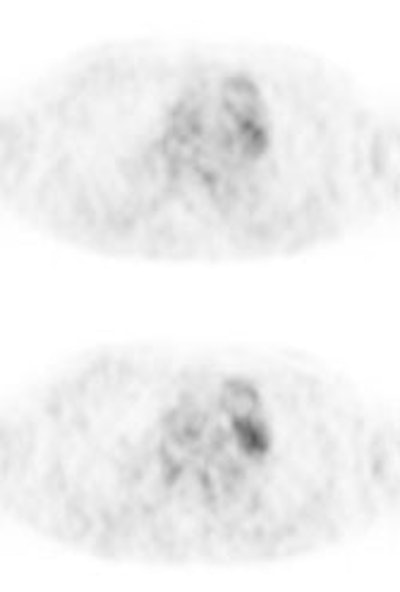

Bronchoalveolar cell carcinoma (BAC): The images below were from a patient with bronchoalveolar cell carcinoma that presented as a chronic right lung infiltrate. The FDG PET exam was positive in this case despite a higher likelihood of a false negative exams in patients with BAC. Note the most intense area of FDG accumulation corresponds to the area of greatest consolidation on CT imaging. |